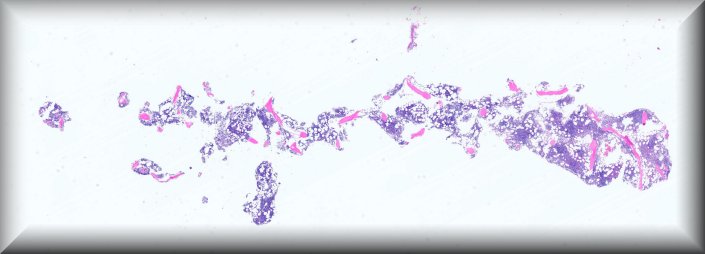

Caso 4.- Paula Tenhaeff Lackschewitz, Gerónimo Llopis, Raquel Martínez Marcos, Esther Roselló Sastre.

Hospital General Universitario de Valencia.

Varón de 28 años, con antecedente de infección por VIH diagnosticada en 2019 y abandonodel tratamiento antirretroviral. Consulta por un mes de evolución de lesiones cutáneas pápulo-nodulares eritematosas y descamativas, tos seca, pérdida ponderal de 10 kg y edemas enextremidades inferiores. En la exploración presenta fiebre de 39 °C, taquicardia y hepatoesplenomegalia. La analítica muestra pancitopenia severa, hipoalbuminemia,hipertransaminasemia y ferritina >90 000 µg/L. Serologías para VHB, VHC, CMV, VEB yBartonella negativas, con beta-D-glucano positivo. Con sospecha de leismaniasis/linfoma serealiza biopsia de médula ósea.